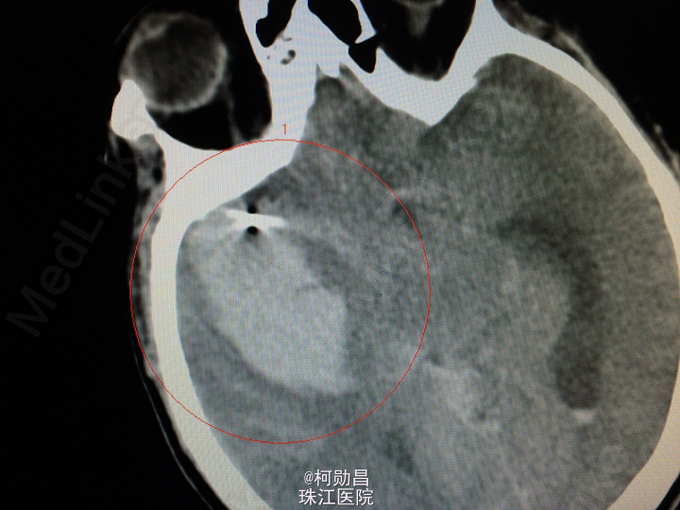

主诉:突发意识障碍7小时 病史:患者于早上7时被发现意识不清,神志呈浅昏迷状态(GCS6分),立即被送往当地医院,急查头颅CT提示:1、右侧颞叶脑出血;2、蛛网膜下腔出血病四脑室积血;3、中线结构轻度左移(0.3cm)。立即予器官插管呼吸辅助通气、止血、抗血管痉挛、维持水电平衡、营养神经的个治疗。后为进一步治疗转入我院。

诊断:蛛网膜下腔出血破入脑室:动脉瘤? 处理:急诊予全脑血管造影提示:右侧大脑中动脉分叉处动脉瘤,予介入栓塞治疗(弹簧圈),并予去骨瓣减压术治疗。